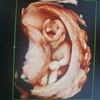

孕晚期会不会出现呼吸困难。有这样的宝妈吗?